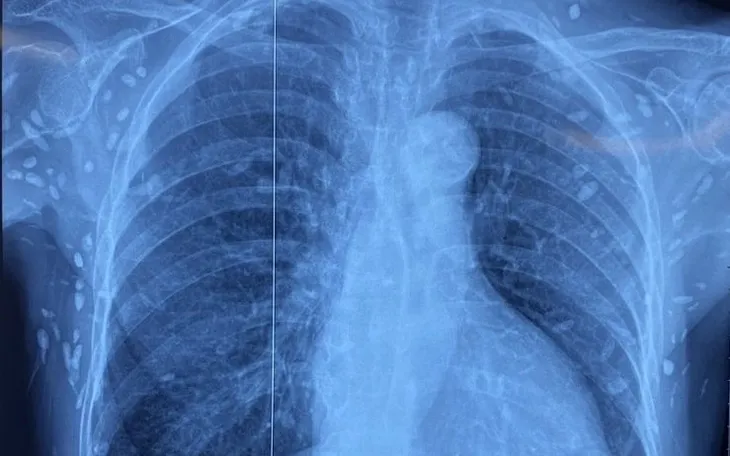

Nhiều nốt cản quang dưới da thành ngực-bụng và chi trên.

Người bệnh được chuyển đến Viện Lâm sàng các bệnh Truyền nhiễm trong tình trạng rối loạn ý thức, đe dọa suy hô hấp. Kết quả chụp cắt lớp vi tính sọ não và X-quang ngực - bụng cho thấy rất nhiều nốt cản quang nằm rải rác trong nhu mô não và dưới da vùng ngực, bụng, tay. Một số u cục có thể sờ thấy bằng tay.